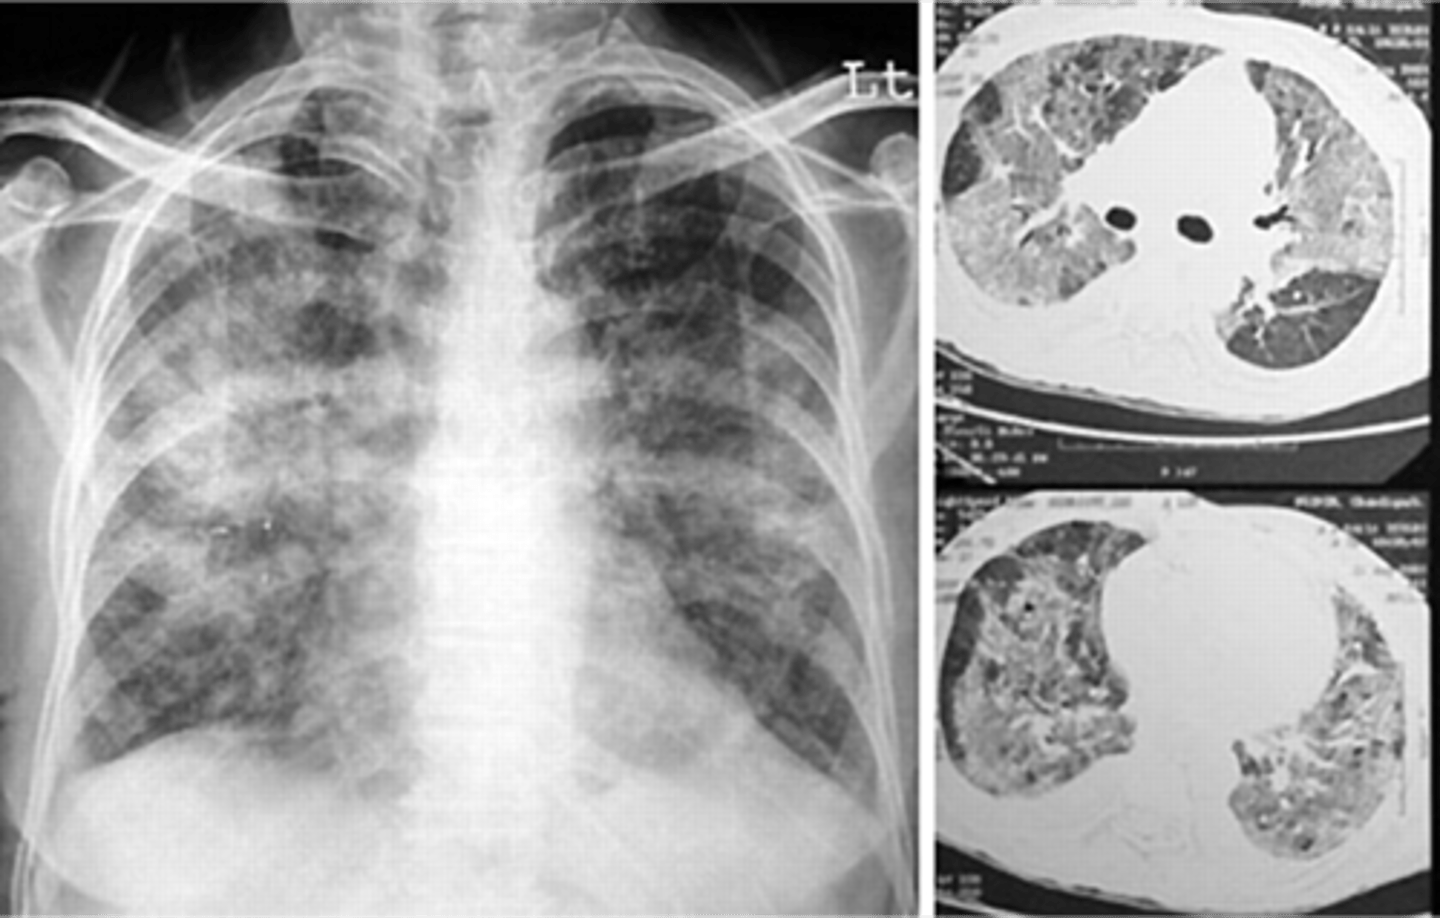

ARDS